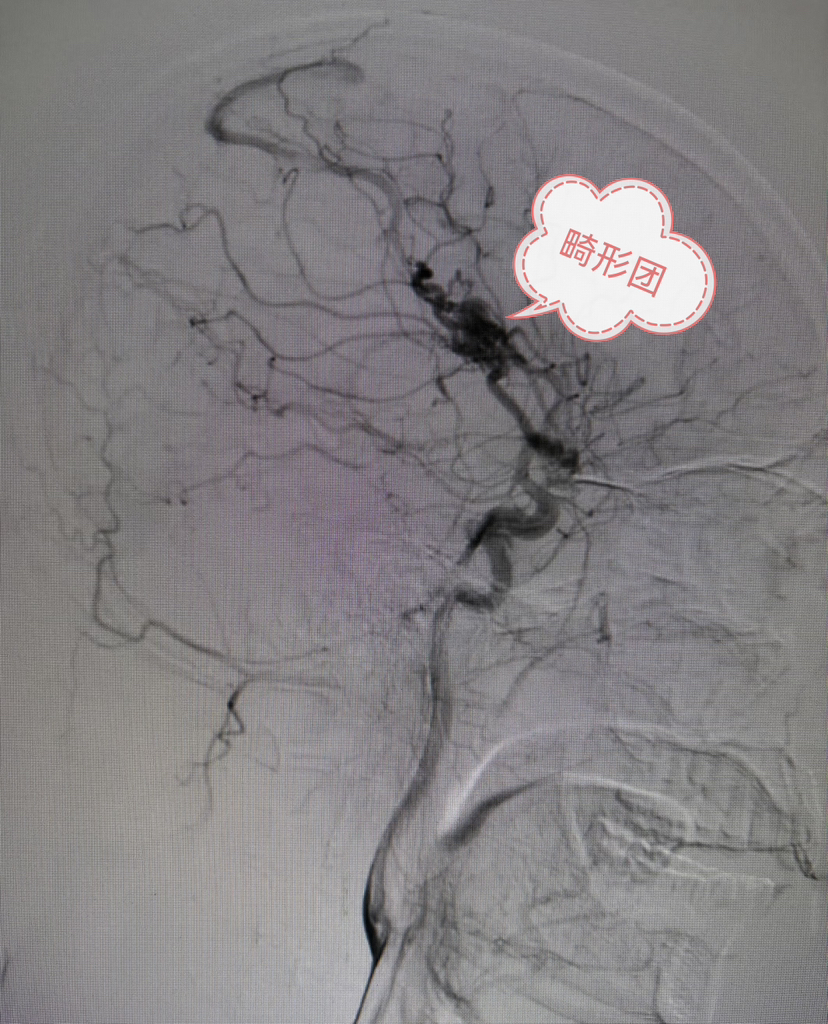

DSA侧位